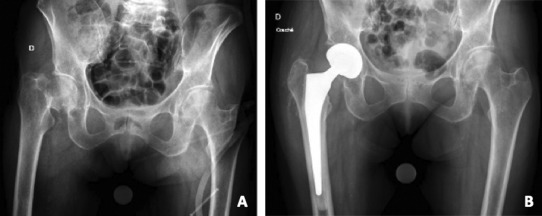

Total Hip Arthroplasty (THA) in FNFs

THA has increasingly been adopted for the management of displaced FNFs in selected patients, particularly those who are younger, higher functioning, and medically fit. Evidence consistently shows that THA offers superior functional outcomes compared to HA, although at the cost of higher complication rates. (Figure 2)

Registry data corroborate these findings with the Swedish registry PROMs consistently reporting higher satisfaction and functional scores after THA compared with HA.20 Conversion of HA to THA for acetabular erosion restores function but carries higher revision and complication rates than primary THA.75 (Figure 3)